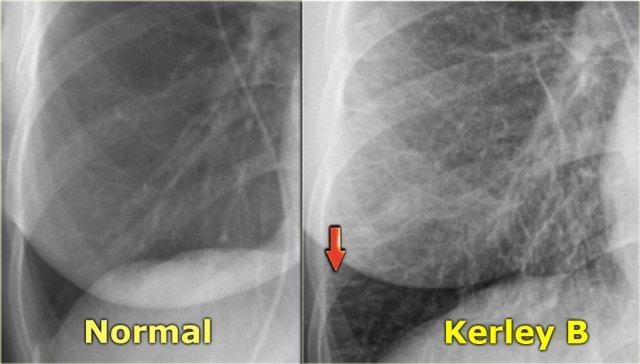

Khi dịch thoát vào các vách liên tiểu thùy ngoại vi, nó được biểu hiện dưới dạng đường Kerley B hay đường vách.

Đường Kerley B được thấy dưới dạng các đường ngang ngắn 1-2 cm ở ngoại vi, gần các góc sườn hoành.

Các đường này chạy vuông góc với màng phổi.

Khi dịch thoát vào mô kẽ quanh phế quản-mạch máu, nó biểu hiện dưới dạng dày thành phế quản (dày bao quanh phế quản) và mất nét bờ của các mạch máu này (mờ quanh rốn phổi).

Bên trái là hình ảnh bệnh nhân suy tim sung huyết.

Có sự tăng khẩu kính của các mạch máu phổi và chúng mất nét bờ do bị bao quanh bởi phù nề.

X-quang ngực bình thường trước đó (trái) và suy tim sung huyết giai đoạn II với mờ quanh rốn phổi (phải)

Bên trái là hình ảnh một bệnh nhân khác bị suy tim sung huyết.

Tư thế chụp nghiêng thể hiện rõ sự tăng đường kính của các mạch máu phổi và bờ mờ nhạt của chúng.

Lưu ý cũng có các đường vách và mô kẽ nổi bật.

Ngoài ra, khe liên thùy lớn dày lên rõ rệt.